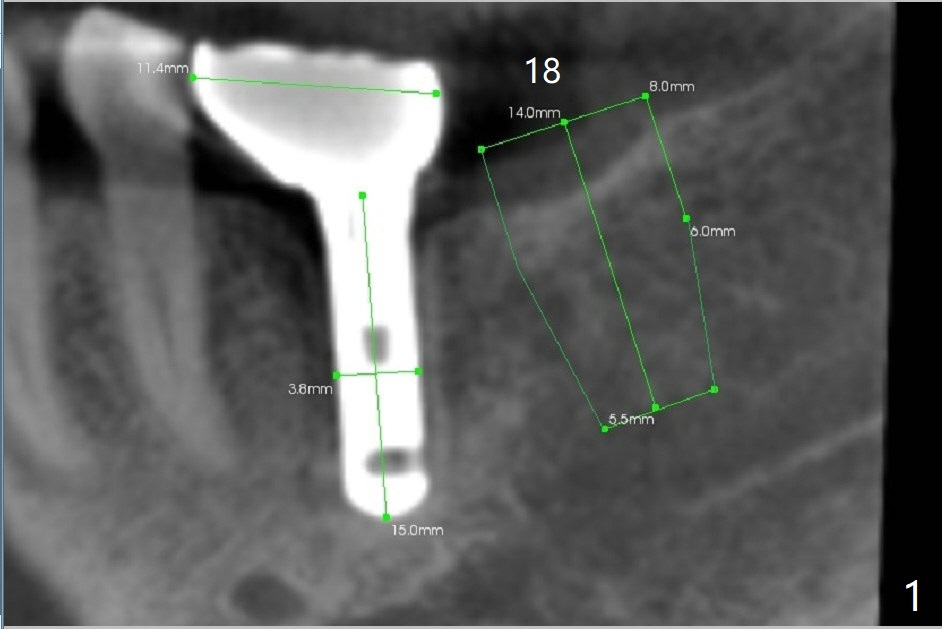

A 69-year-old man needs an implant at #18 (Fig.1,2 CT (sagittal and coronal sections)). In spite of use of surgical stent, the trajectory is not ideal (Fig.3-5). The following day the implant is removed with bone graft (Fig.6). In the 2nd placement, the trajectory is adjusted in each step (Fig.7-9 arrows) with long term stability (Fig.10,11).